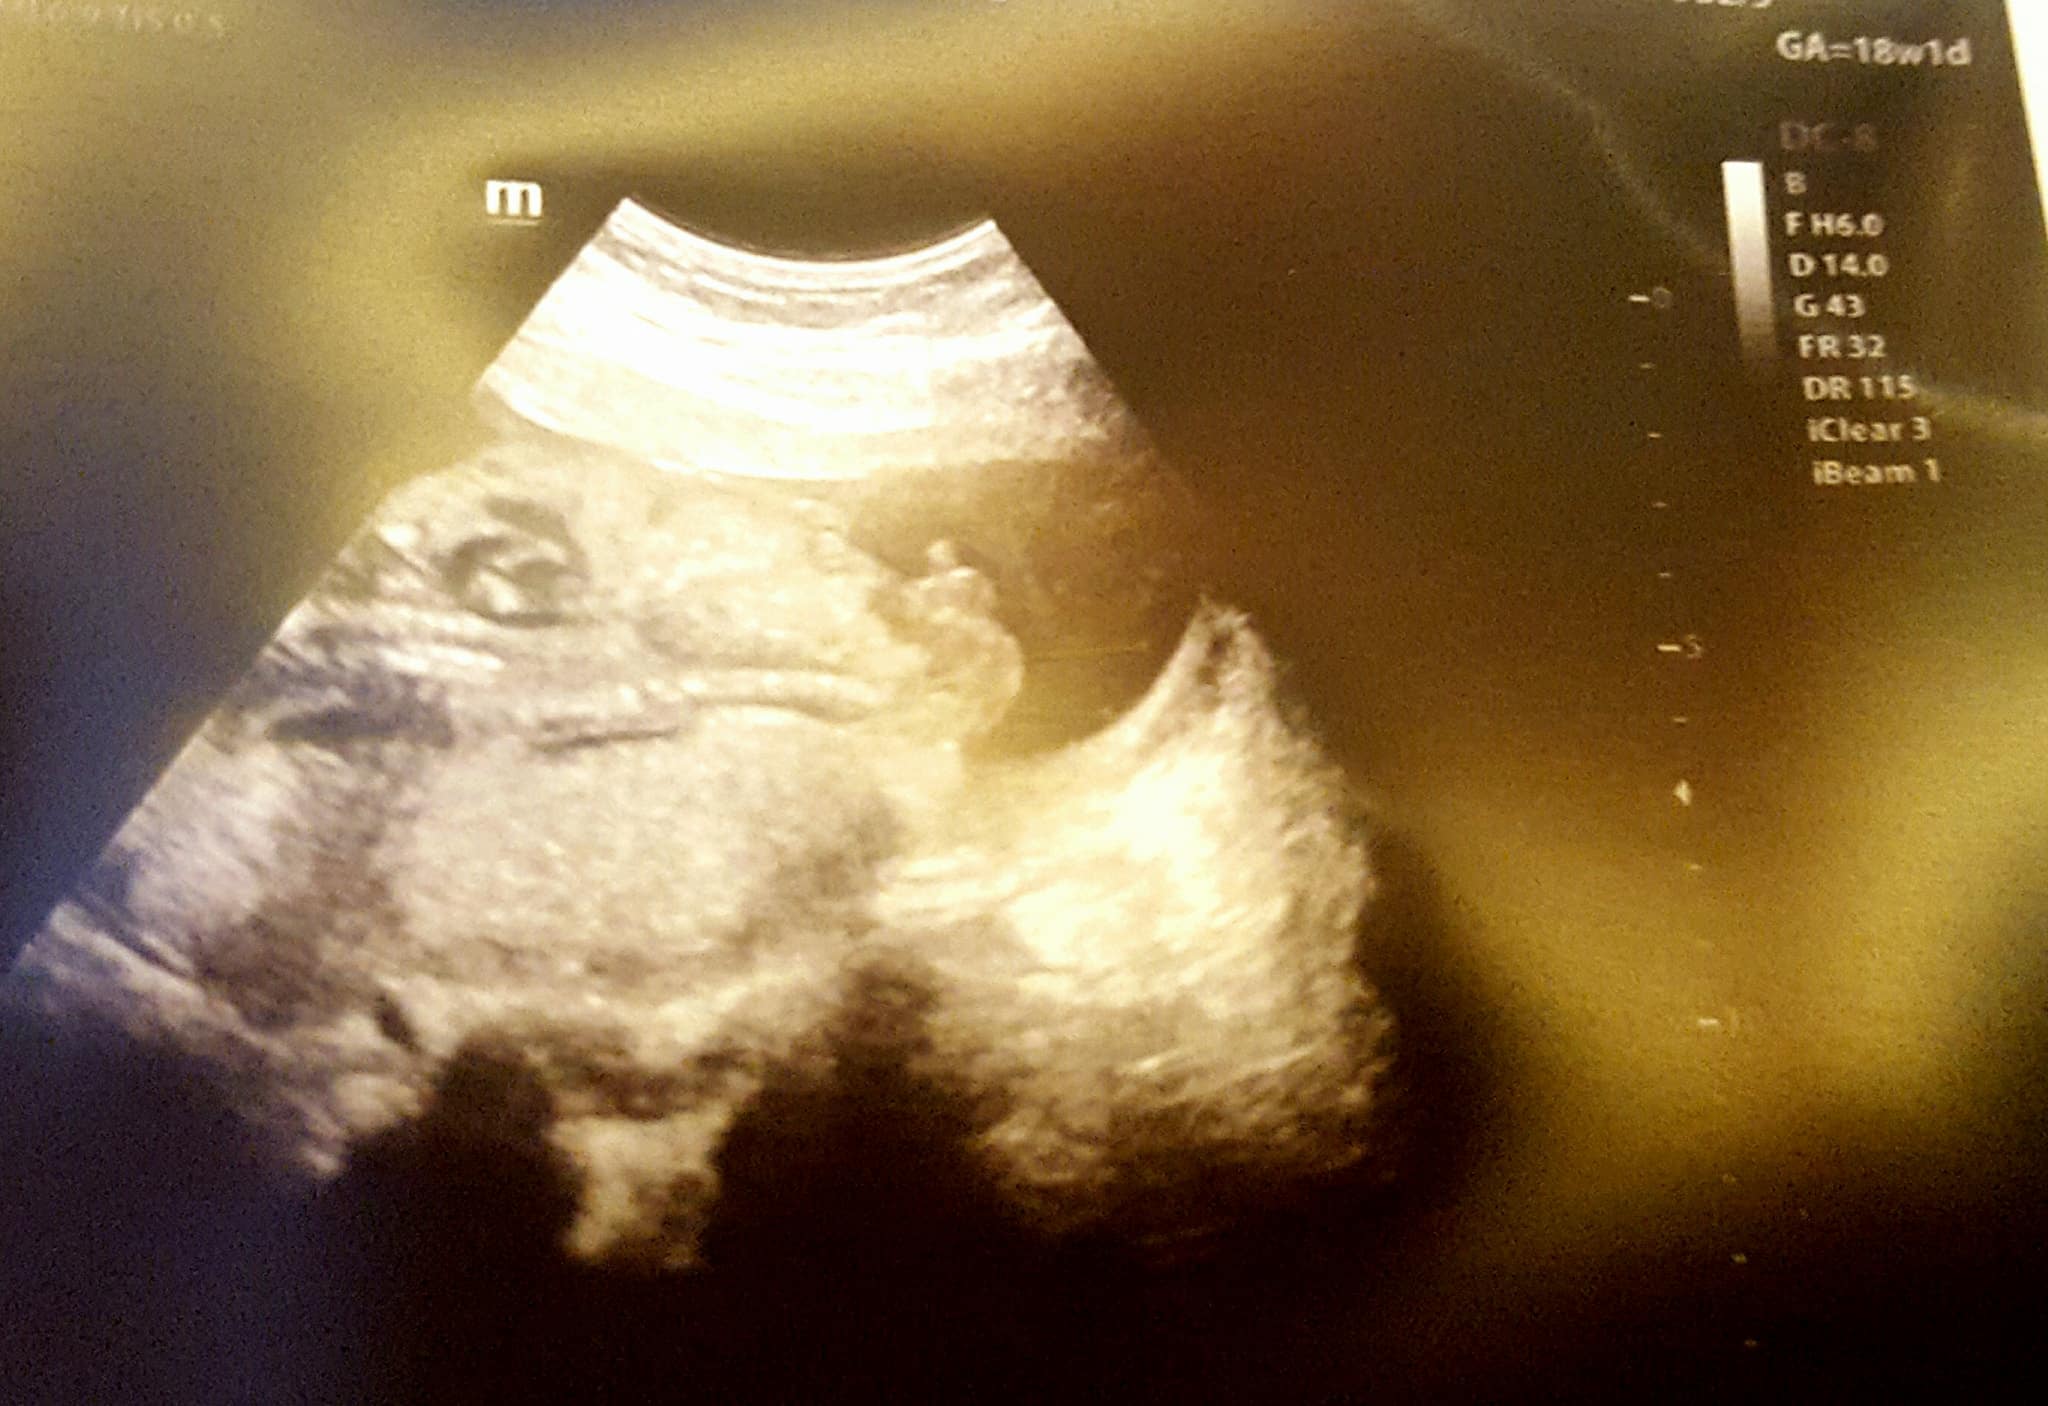

Here is my 18weeks scan. 1 picture looks boyish and 1 girlish :( Both are same day picture. Its confusing. I will have my Gender scan in 2 weeks. Any thoughts?

Attachment 38472

Top pic, BOY. The second pic is so far away that it's not a good shot of his goods but it still looks boyish to me. Didn't you have a blood test done to determine gender? I would believe that. Congrats on your BOY!!!

Top pic is obvious boy, the second pic is botched and just a bad pic. The techs can move their focus in or out and they just didn't capture the goods, that's all. :)